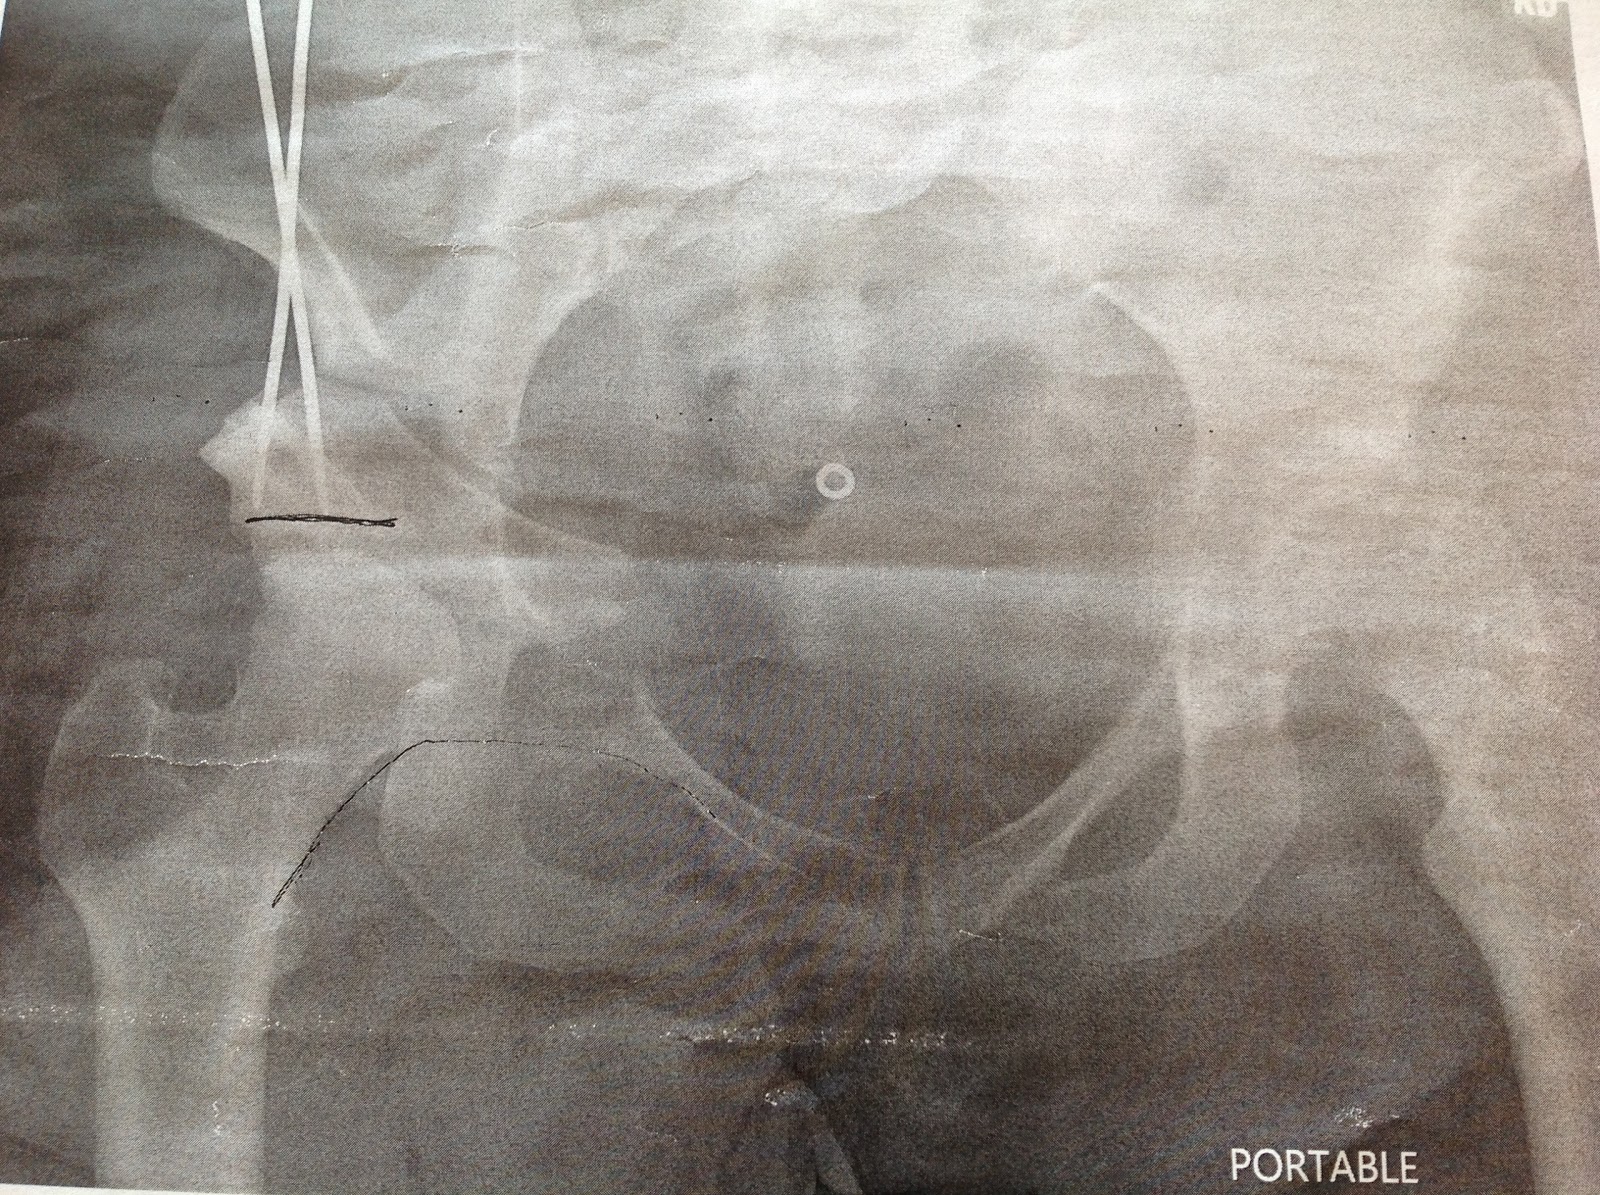

X-Ray of PAO Hip Reconstruction and Hip Dyplasia

X-Rays from the day of my surgery, 03/29/2013 (over 1 year ago). Never posted it to my blog! Here's a before, and kind of after. The screws aren't in place yet, but that is the exact placement they did. I now have a total of 3 screws holding the placement. According to the CT scan that I had on Wednesday, everything looks good. The reconstruction is still in place and healing well. However, because I had such a big correction there will be a part of my bone that will not grow back together (non-union). They said that it should be ok, and doesn't need extra surgery at this time. The fracture I got last year seems to be calcifying and healing as well.